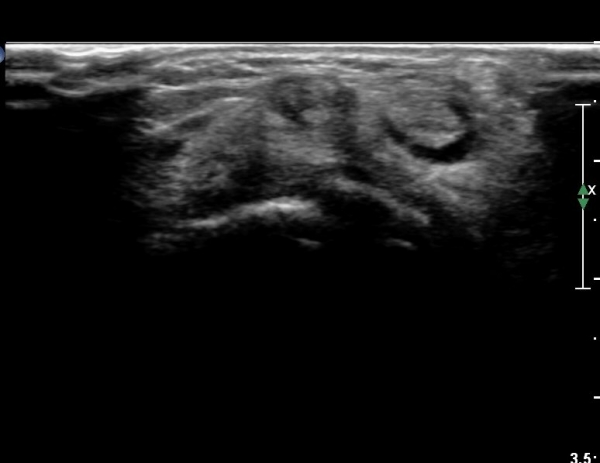

¿ä°ñ ¸»´Ü lister's tubercle ºÎÀ§¿¡¼­ Àå, ´Ü¿äÃø¼ö±Ù½ÅÀü°Ç Ⱦ´Ü¸é°Ë»ç¿¡¼­ ƯÀÌ ¼Ò°ßÀ» º¸ÀÌÁö

¾Ê´Â´Ù(»çÁø 3).